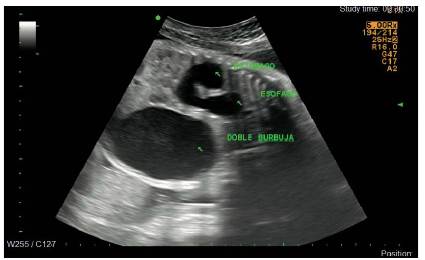

En una ecografía de seguimiento realizada en la semana 31, además se logra evidenciar en el mediastino, una imagen anecoica no vascularizada al Doppler color, con relación a dilatación esofágica en el tercio distal, la cual se asoció a polihidramnios, con lo que se hizo una impresión diagnóstica de atresia esofágica asociada (Figuras 3 y 4).

Existen otras anomalías gastrointestinales (diferentes a los defectos anorrectales) que se asocian a la presencia de atresia gastroesofágica/fístula traqueoesofágica, como lo es la atresia duodenal, la cual, aunque no se encuentra incluida dentro de la definición de la asociación VACTERL, se ha reportado hasta en el 5 % de los casos 2,7. Dicha anomalía tiene incidencia de 1 en 2.500 a 5.000 nacidos vivos. Ocurre usualmente en la segunda porción del duodeno. El diagnóstico ecográfico prenatal ha sido reportado en el 87 % de los fetos afectados, en su mayoría por la detección del signo de doble burbuja intraabdominal; también se pueden evidenciar polihidramnios en el 40 % de los casos a partir del segundo trimestre. Los signos ecográficos son relativamente lentos en desarrollarse, pero el signo de doble burbuja abdominal puede observarse tan pronto como a las 12 semanas de gestación 10,14.

En una serie de 114 casos reportados por Ladd y Swenson se describe la incidencia de la asociación entre atresia esofágica y atresia duodenal en aproximadamente 5 % de los casos de la asociación VACTERL, y es aún más baja la incidencia asociando además el ano imperforado, como lo es en el caso presentado 12. Teóricamente el diagnóstico de la atresia esofágica con fístula traqueoesofágica, atresia duodenal y malformación anorrectal puede realizarse de manera prenatal, con confirmación con estudio radiológico de tórax y abdomen en el neonato; sin embargo, hay gran dificultad especialmente cuando se trata de una atresia esofágica pura 15; en nuestro caso se reporta una atresia esofágica tipo 1. Identificamos varios casos en la literatura que se realizan en diagnóstico prenatal de atresia esofágica tipo 1 con atresia duodenal 16-19; no obstante, solo en uno, así como en nuestro caso, se logran evidenciar todos los hallazgos eco-gráficos típicos, que incluyen polihidramnios, dilatación esofágica distal y signo de la doble burbuja intraabdominal 17.